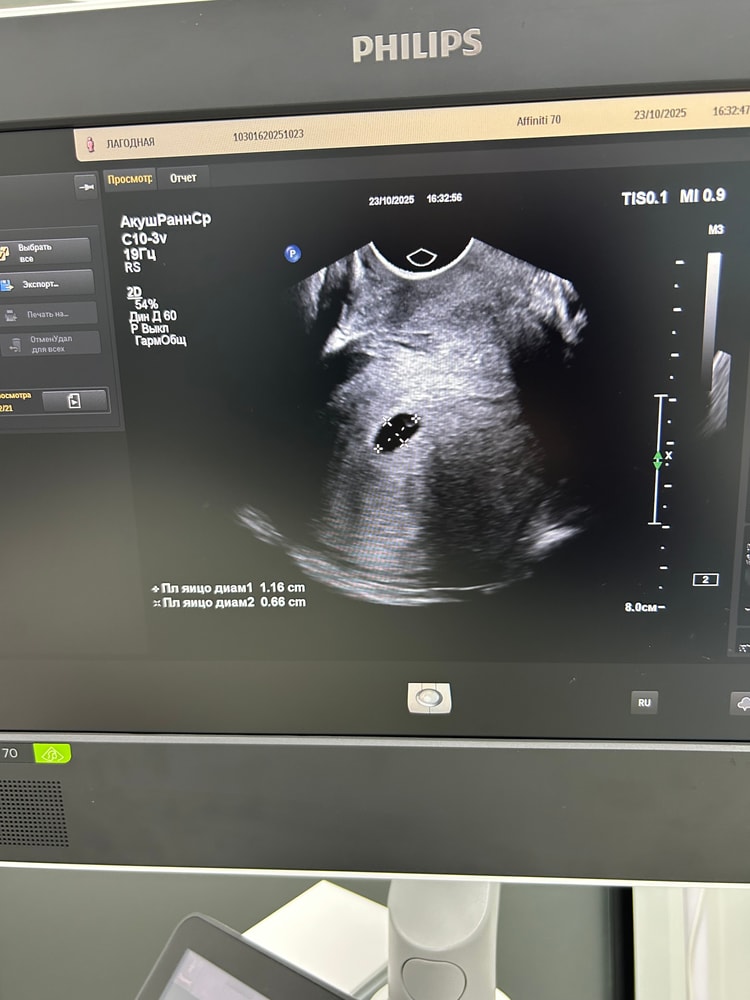

УЗИ, КТГ, доплерБеременность маточная, сроку соответствует 6 недель, но эмбриончика не видно, желточный мешочек есть, формы четкие и ровные, я немного расстроилась ,тк хотела сб послушать 🥹

а вот моя бусинка🩷